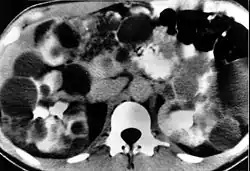

Nerki

W nerkach pacjentów z zespołem von Hippla-Lindaua rozwijają się zmiany nienowotworowe o charakterze torbieli prawdziwych (cystes renis), zmiany nowotworowe łagodne o charakterze torbielakogruczolaków (cystadenomata) i nowotwory złośliwe – rak nerkowokomórkowy (carcinoma renocellulare). Torbiele nerek są bezobjawowe. Rak nerki rozwija się w obrębie torbieli, zazwyczaj jest to rak jasnokomórkowy (clear-cell carcinoma). W zespole von Hippla-Lindaua dotyczy ponad 70% pacjentów[1] – jest to najczęstsza przyczyna rodzinnego występowania nowotworu złośliwego nerki. Rozwija się w młodym wieku, często obustronnie i wieloogniskowo; późno daje przerzuty.